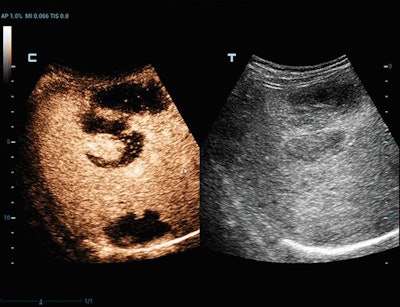

Contrast-enhanced ultrasound scan of liver lymphoma, using Ultra-Wideband Non-Linear (UWN+) technology. Image courtesy of Mindray.

Contrast-enhanced ultrasound scan of liver lymphoma, using Ultra-Wideband Non-Linear (UWN+) technology. Image courtesy of Mindray.Samsung is highlighting a software package, SonoSync. The software provides network service to transmit real-time ultrasound examinations so that clinicians at different locations can view images simultaneously. SonoSync can be connected to smartphones, tablets, laptops, and desktop PCs.